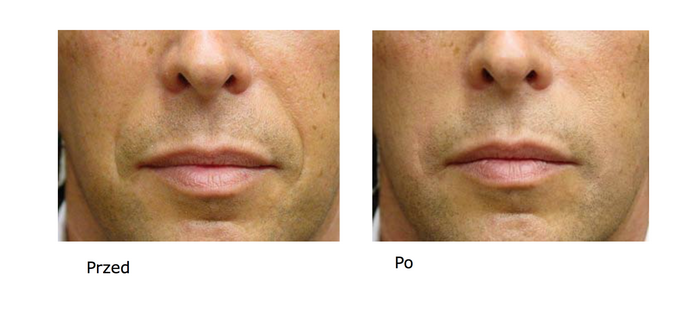

Bardzo wiele osób decyduje się na zmianę swojego wizerunku. Kopmleksy, które mamy często nie dają …

Potrzeba emanowania pięknem towarzyszy przedstawicielkom płci żeńskiej od czasów zamierzchłych. Oczywiście również mężczyźni troszczą się …